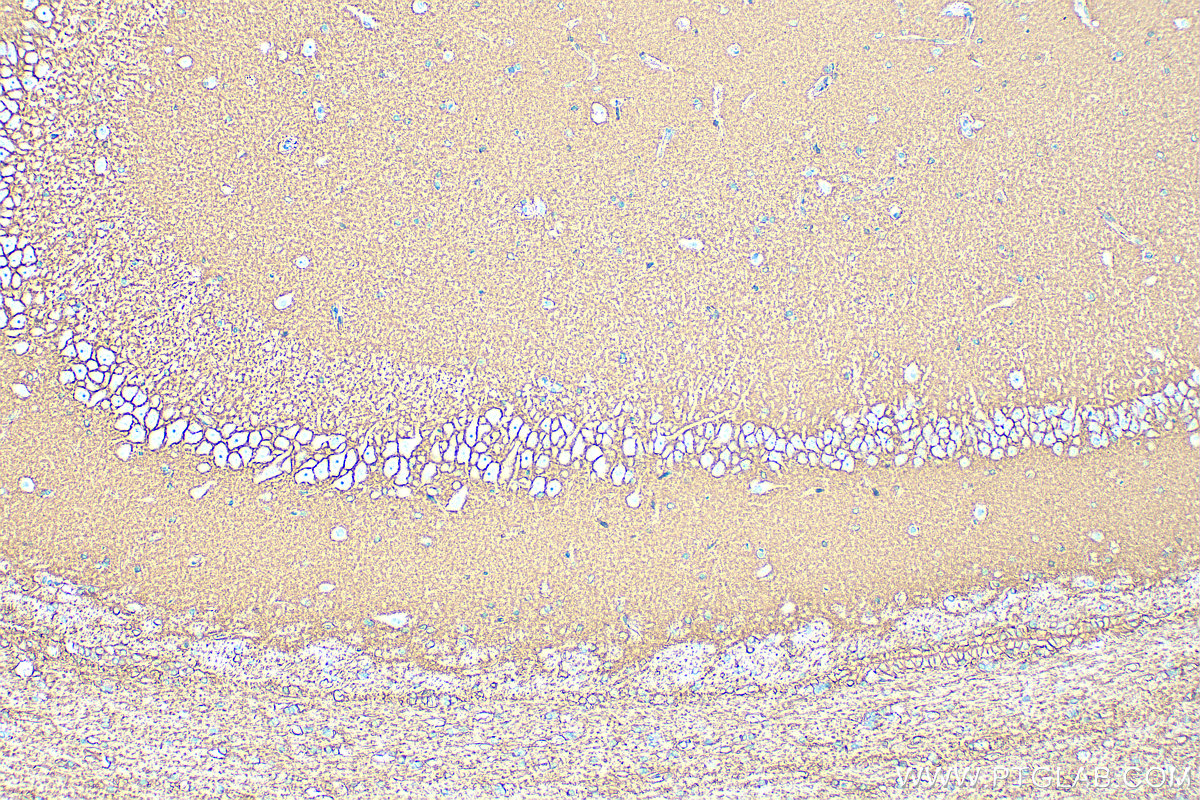

| Positive IHC detected in | mouse brain tissue, rat brain tissue Note: suggested antigen retrieval with TE buffer pH 9.0; (*) Alternatively, antigen retrieval may be performed with citrate buffer pH 6.0 |